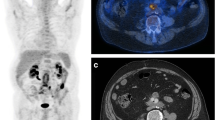

Vascular graft infection (VGI) in central grafts is a rare but dreaded complication with a high mortality. Several imaging modalities are employed, all with pros and cons. Computed tomography is the standard, but lacks sensitivity for low-grade infections. There is still no consensus regarding the diagnostic modality of choice. The study objective was to assess the role of combined positron emission tomography and computed tomography with fluorodeoxyglucose (FDG-PET/CT) in the diagnostic workup of VGI in central grafts.

In recent years, molecular imaging with fluorine-18-labeled fluorodeoxyglucose-positron emission tomography/computed tomography (FDG-PET/CT) is increasingly explored in infectious disease, as the glucose-analog FDG also accumulates at sites with a high glucose turnover due to infection and inflammation [6, 7]. Contrary to earlier stand-alone PET, hybrid PET/CT enables a more precise differentiation between soft tissue and graft infection and makes FDG-PET/CT a potentially more useful diagnostic tool [1, 4, 6,7,8]. However, the physiologic reactive FDG uptake along the graft material may hamper the diagnostic accuracy in VGI with FDG-PET/CT [9]. Several studies are available on the use of FDG-PET/CT in VGI, and new data are added regularly, but controversy still remains on the diagnostic strategy, including which interpretation schemes to use, albeit four different parameters are employed, i.e., focal uptake, visual grading scale (VGS), maximum standardized uptake value (SUVmax), and tissue-to-background ratio (TBR).